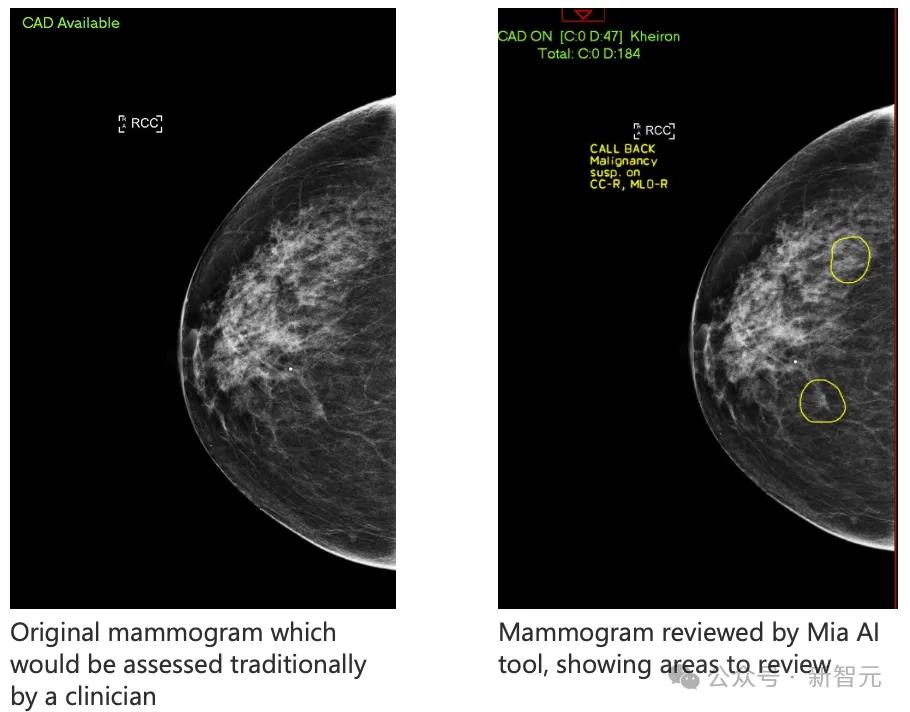

AI工具Mia在乳腺X光检查扫描中,圈出了两个关键区域

大家都知道,乳腺癌在早期很难发现,但是最近,一个名叫Mia的AI工具,就成功地在11名女性的乳腺X光检查中,发现了被人类医生遗漏的微小迹象!

在分析了10000多名女性的乳腺X光检查后,Mia成功地标记出了所有有癌症症状的人,并且发现了人类医生没有发现的11名乳腺癌早期患者。